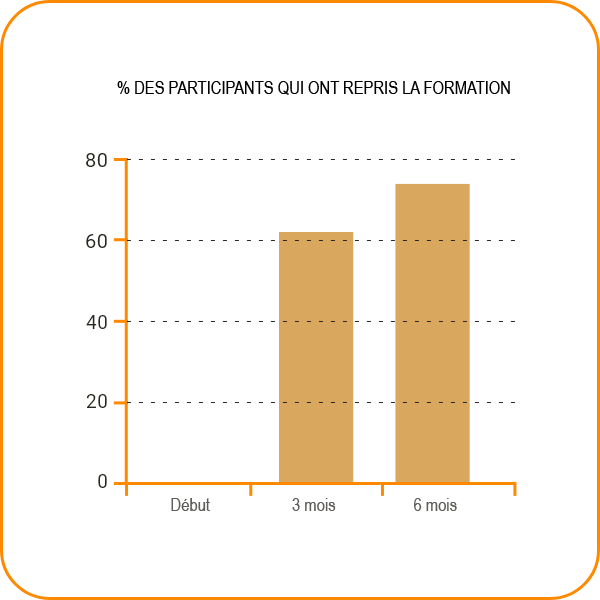

Avec l'aide de TENDOFORTE®, 12 des 18 participants à l'étude ont repris la course à pied en seulement trois mois. La supplémentation a amélioré la stabilité et la fonction du tendon d'Achille, tout en réduisant la douleur.